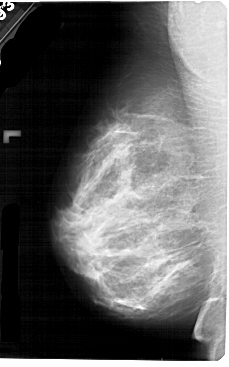

A_1752_1.LEFT_MLO

LEFT_MLO LINES 5491 PIXELS_PER_LINE 3421 BITS_PER_PIXEL 12 RESOLUTION 43.5 NON_OVERLAY